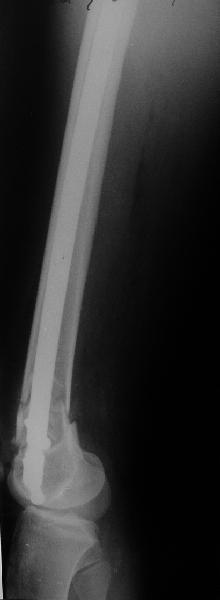

А в чем проблемы? Пример в приложении.

Насчет снимка Вами представленного - смотрится оч красиво, еще бы на функцию узнать...

В приложении функциональные снимки в 3 мес. и в 1 год.